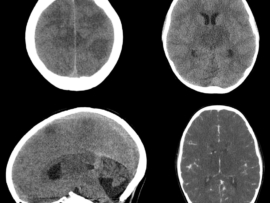

A term, appropriate-for-gestational-age neonate with normal APGAR scores and no history of perinatal hypoxia presented with seizures on day 2 of life.